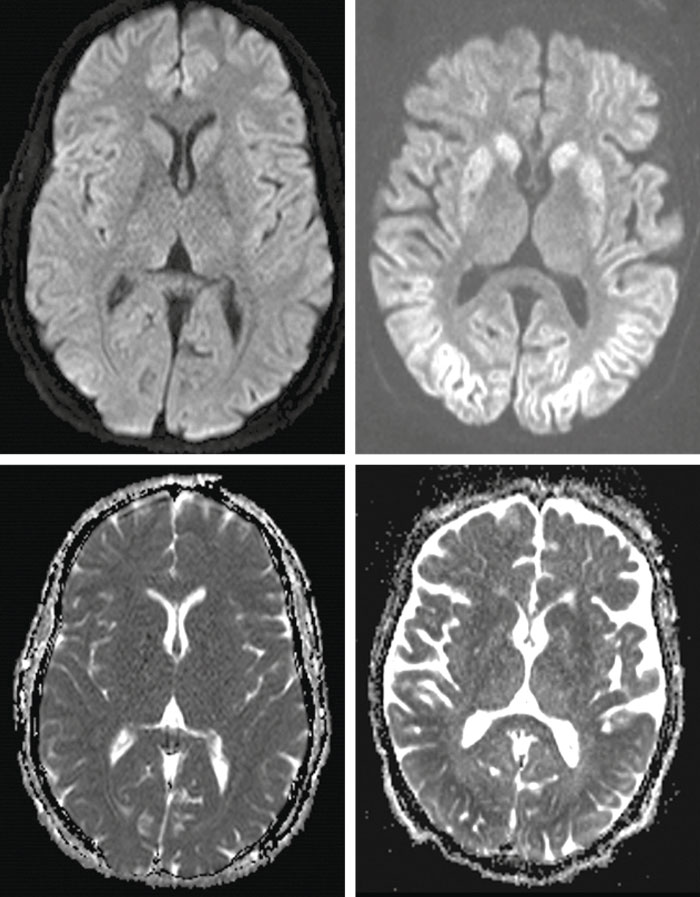

Efter fullbordad ischemi uppstår ett generellt cyto­toxiskt ödem i hjärnan som gör att grå substans i kortex och basala ganglier avgränsas dåligt eller inte alls från vit substans på datortomografi (DT) (Figur 3). Minskad kvot mellan täthet i grå och vit substans har stark koppling till dåligt utfall om förändringarna är utbredda och uppträder inom 24 timmar. Sensitiviteten varierar dock starkt beroende på vilka gränsvärden som tillämpas. Med kvoten mellan täthet i grå och vit substans tillräckligt lågt satt för falskt positiv frekvens (0–4 procent) har sensitiviteten visat sig vara mycket låg: 3,5–20 procent i färska studier [33, 34].

Mindre uttalade ischemiska/anoxiska förändringar är ofta svåra att påvisa och bedöma med hjälp av DT, och för neurologisk prognosbedömning rekommenderas främst undersökning med magnetresonans (MR) 3–5 dagar efter hjärtstoppet, eftersom MR-bil­den utvecklas över tid. Diffusionsviktade bilder med beräknad »apparent diffusion coefficient« (ADC), som avspeglar medeldiffusionen i varje bildelement, är överlägsna konventionella MR-sekvenser för att påvisa akuta hypoxiska/ischemiska lesioner.

Den nedsatta diffusionen i sådana områden ger hög signalintensitet (vitt) på diffusionsviktade bilder och låg signalintensitet (svart) på kvantitativ ADC-karta (Figur 4). Bilaterala utbredda eller multipla lesioner med nedsatt diffusion i kortex, djup grå substans och lillhjärna är förknippade med dålig prognos.

I en nyare studie med strukturerad visuell skattning av akuta diffusionslesioner nådde man 0 procent falskt positiv frekvens och 55–60 procents sensitivitet för dåligt utfall [35]. I studier med ADC-mätning har låga värden i olika regioner eller i hela hjärnan associerats till dålig prognos. Nyligen fann man vid retrospektiv semiautomatisk diffusionsanalys i en multi­centerkohort med 125 patienter att ADC <650 × 10-6 mm2/s i minst 10 procent av hjärnans volym gav 9 procent falskt positiv frekvens och 72 procents sensitivitet för dåligt utfall [36].

Icke desto mindre är tillgängliga MR-studier analystekniskt heterogena, och för såväl diffusionsviktade som ADC-baserade mätningar saknas säkra tröskelvärden för prognosbedömning i klinisk vardag.

Figur 3. Ischemiska/anoxiska skador i hjärna efter hjärtstopp visualiserade med datortomografi. Till vänster: normal bild; till höger: cytotoxiskt ödem med utplånad skillnad mellan vit och grå substans.